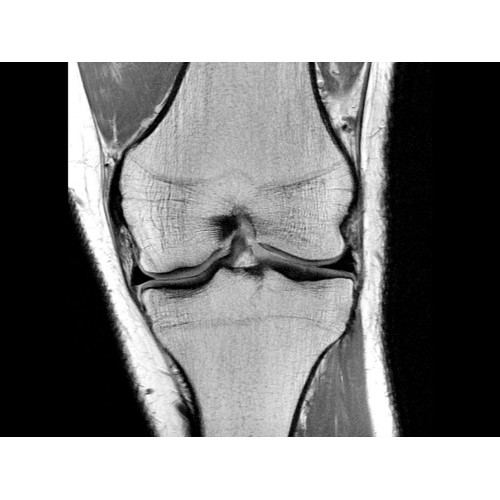

МР-томограф Optima MR450w позволяет получать изображения исключительно высокого качества, которые помогают установить диагноз. Чтобы удовлетворить ожидания клиентов в отношении высокого качества, в МР-томографе Optima MR450w были сохранены дополнительные возможности платформы Discoverу, привнесшие в его работу универсальность и мощь.

• РЧ-катушки, оптимизированные для исследования конкретных участков тела — элементы катушек высокой плотности располагаются вокруг исследуемых участков тела и при необходимости обеспечивают расширенный охват и оптимальное качество изображений при каждой процедуре.

• Широкое поле зрения — поле зрения шириной 50 см позволяет охватывать крупные анатомические области за меньшее число сканов.